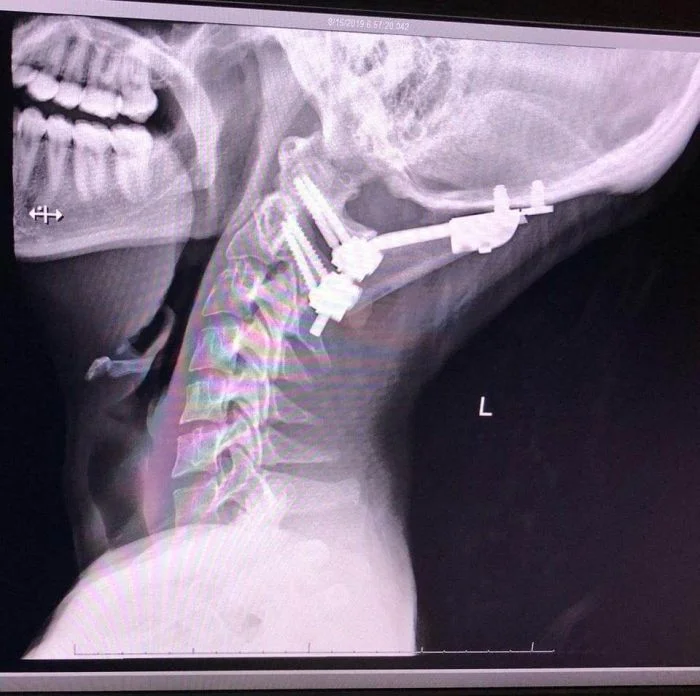

Медицинское приспособление для лечения перелома шеи